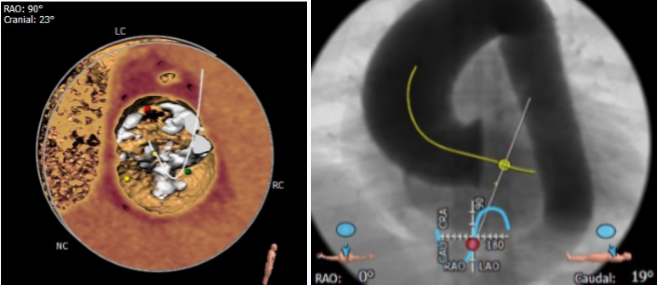

瓣叶分型

根据瓣环的截面分析,

二叶瓣Type1,极重度钙化,可见右无有钙化脊

可根据术中球囊扩张决定

是否Down size

确认冠脉风险

冠脉高度尚可,冠脉平面无可见瓣叶

对侧距离大于30

确认冠脉情况